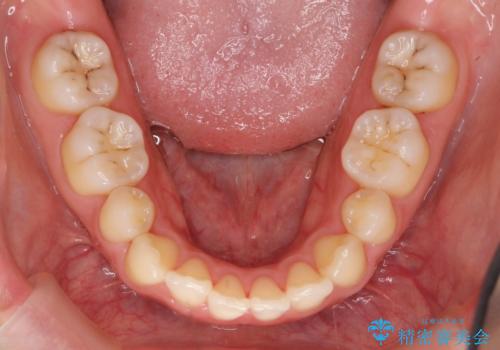

再矯正 昔ワイヤーで治療 前歯の並びを再度きれいに

- 小さいころに小臼歯を抜歯しワイヤー矯正をしたが、すき間が空いてきて、前歯の並びが戻ってしまったとのこと。

インビザラインライトという部分矯正コースで、全体矯正に比べ、比較的安価に治療しました。

前歯の並びが格段にきれいになり、大変喜んでいただけました。